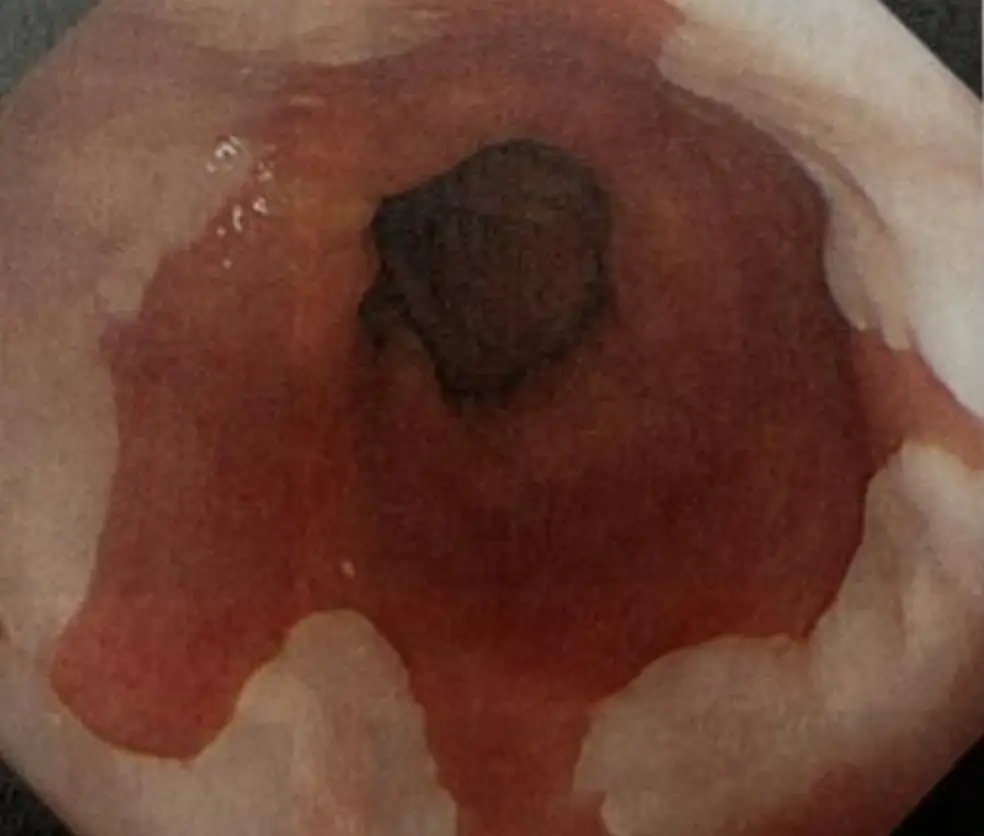

患者因長期胸口灼熱(heartburn)及胸痛接受上消化道內視鏡檢查,結果如圖,下列何者和此病灶的發生無 關?

內視鏡畫面可見管腔中央為暗色吞噬孔,周圍黏膜呈大片暗紅、滲血樣充血並帶有黏膜剝脫,分佈呈環狀且跨越齒狀線,屬典型侵蝕性食道炎 Los Angeles C–D 級影像。未見胃皺襞,顯示此處為遠端食道而非胃體。此類廣泛黏膜發炎符合長期酸/膽汁逆流刺激所致。